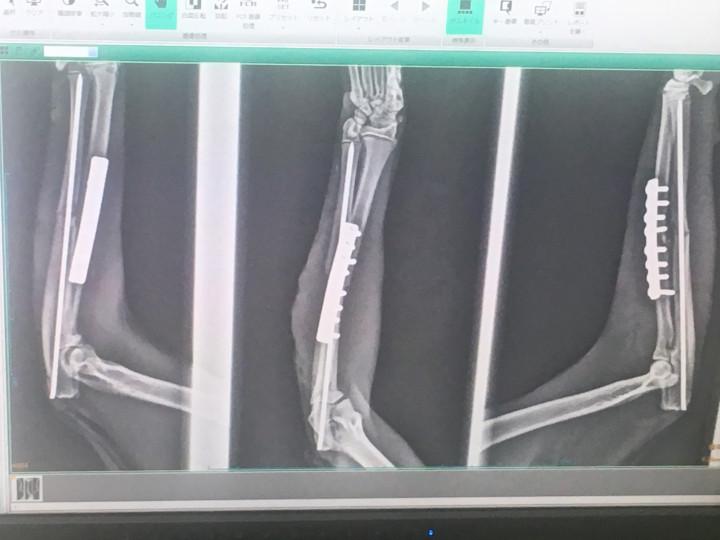

肝心の骨折は、プレート法という術法で、患部を切開してプレートを沿わせ、ピンで固定するというもの。

手術前の骨の状態。

ポッキリ。

そしてプレート埋め込み。

で、手術後の状態がこれ。

しっかりズレが矯正されてます。

後は、激しく動かなければ数ヶ月でしっかりくっつくそう。